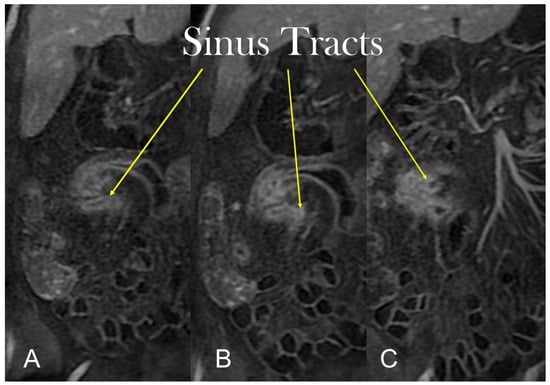

Transmural involvement can develop a sinus tract that reaches the serosa resulting in a fistula’s channel that connects different structures (e.g., entero-enteric, entero-vesical, and entero-vaginal fistula). In fact, sinus passages are closed off from perforations that result in phlegmons or, if infected, abscesses, but do not affect the nearby organs or the skin (Figure 7 and Figure 8).

Figure 7.

The sinus tracts that represent a sealed-off perforation that develops into a phlegmon or, if infected, into an abscess (9) but does not reach adjacent organs or the skin. Therefore, they end up blind.

Figure 8.

Coronal (A–C) contrast-enhanced fat-suppressed T1-weighted images of the same patient show the sinus tracts that represent a sealed-off perforation that develops into a phlegmon or, if infected, into an abscess (9) but does not reach adjacent organs or the skin. Therefore, they end up blind.